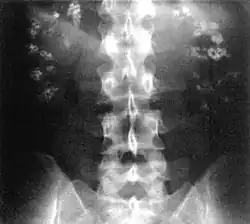

| Bilateral nephrocalcinosis seen on an abdominal x-ray | |

Nephrocalcinosis, once known as Albright's calcinosis after Fuller Albright, is a term originally used to describe the deposition of poorly soluble calcium salts in the renal parenchyma due to hyperparathyroidism. The term nephrocalcinosis is used to describe the deposition of both calcium oxalate and calcium phosphate.[1] It may cause acute kidney injury. It is now more commonly used to describe diffuse, fine, renal parenchymal calcification in radiology.[2] It is caused by multiple different conditions and is determined by progressive kidney dysfunction. These outlines eventually come together to form a dense mass.[3] During its early stages, nephrocalcinosis is visible on x-ray, and appears as a fine granular mottling over the renal outlines. It is most commonly seen as an incidental finding with medullary sponge kidney on an abdominal x-ray. It may be severe enough to cause (as well as be caused by) renal tubular acidosis or even end stage kidney disease, due to disruption of the kidney tissue by the deposited calcium salts.